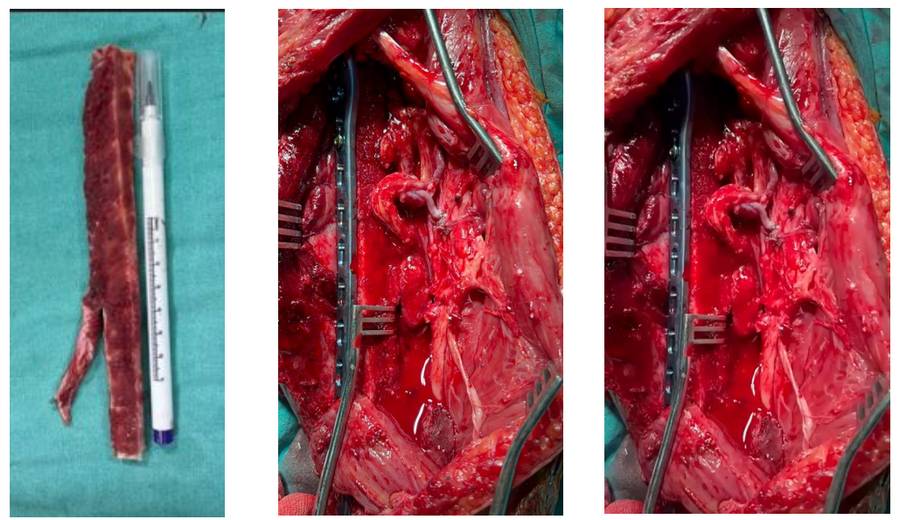

Ameliyat Esnası: Çıkarılan tümör dokusunun klinik ve skopi görüntüsü görülmekte

Ameliyat Esnası: Rezeksiyon sonrası oluşan boşluk ile damar sinir dokuları görülmekte

Ameliyat Esnası: Alınan vaskülerize fibula dokusu, anasyomoz edilmesi ve akım görülmekte